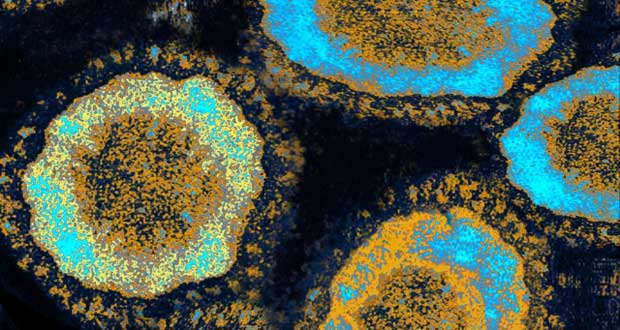

Le coronavirus se transmet sans doute entre humains selon l'OMS